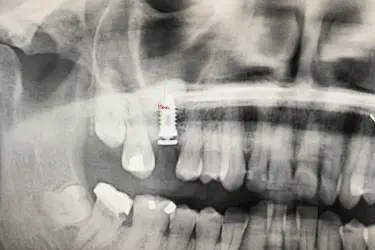

El mismo día de la cirugía el implantólogo realiza una elevación del seno maxilar y posterior injerto de hueso dental artificial.

El odontólogo levanta la membrana del seno maxilar para introducir del material de relleno que aumentará la cantidad y la calidad del hueso del paciente.

Después de la osteointegración del implante, el paciente acude a revisión para ver el estado del hueso artificial injertado.

La altura del hueso maxilar es ahora de 15 mm lo que ha permitido la colocación del implante dental con poco hueso inicialmente.